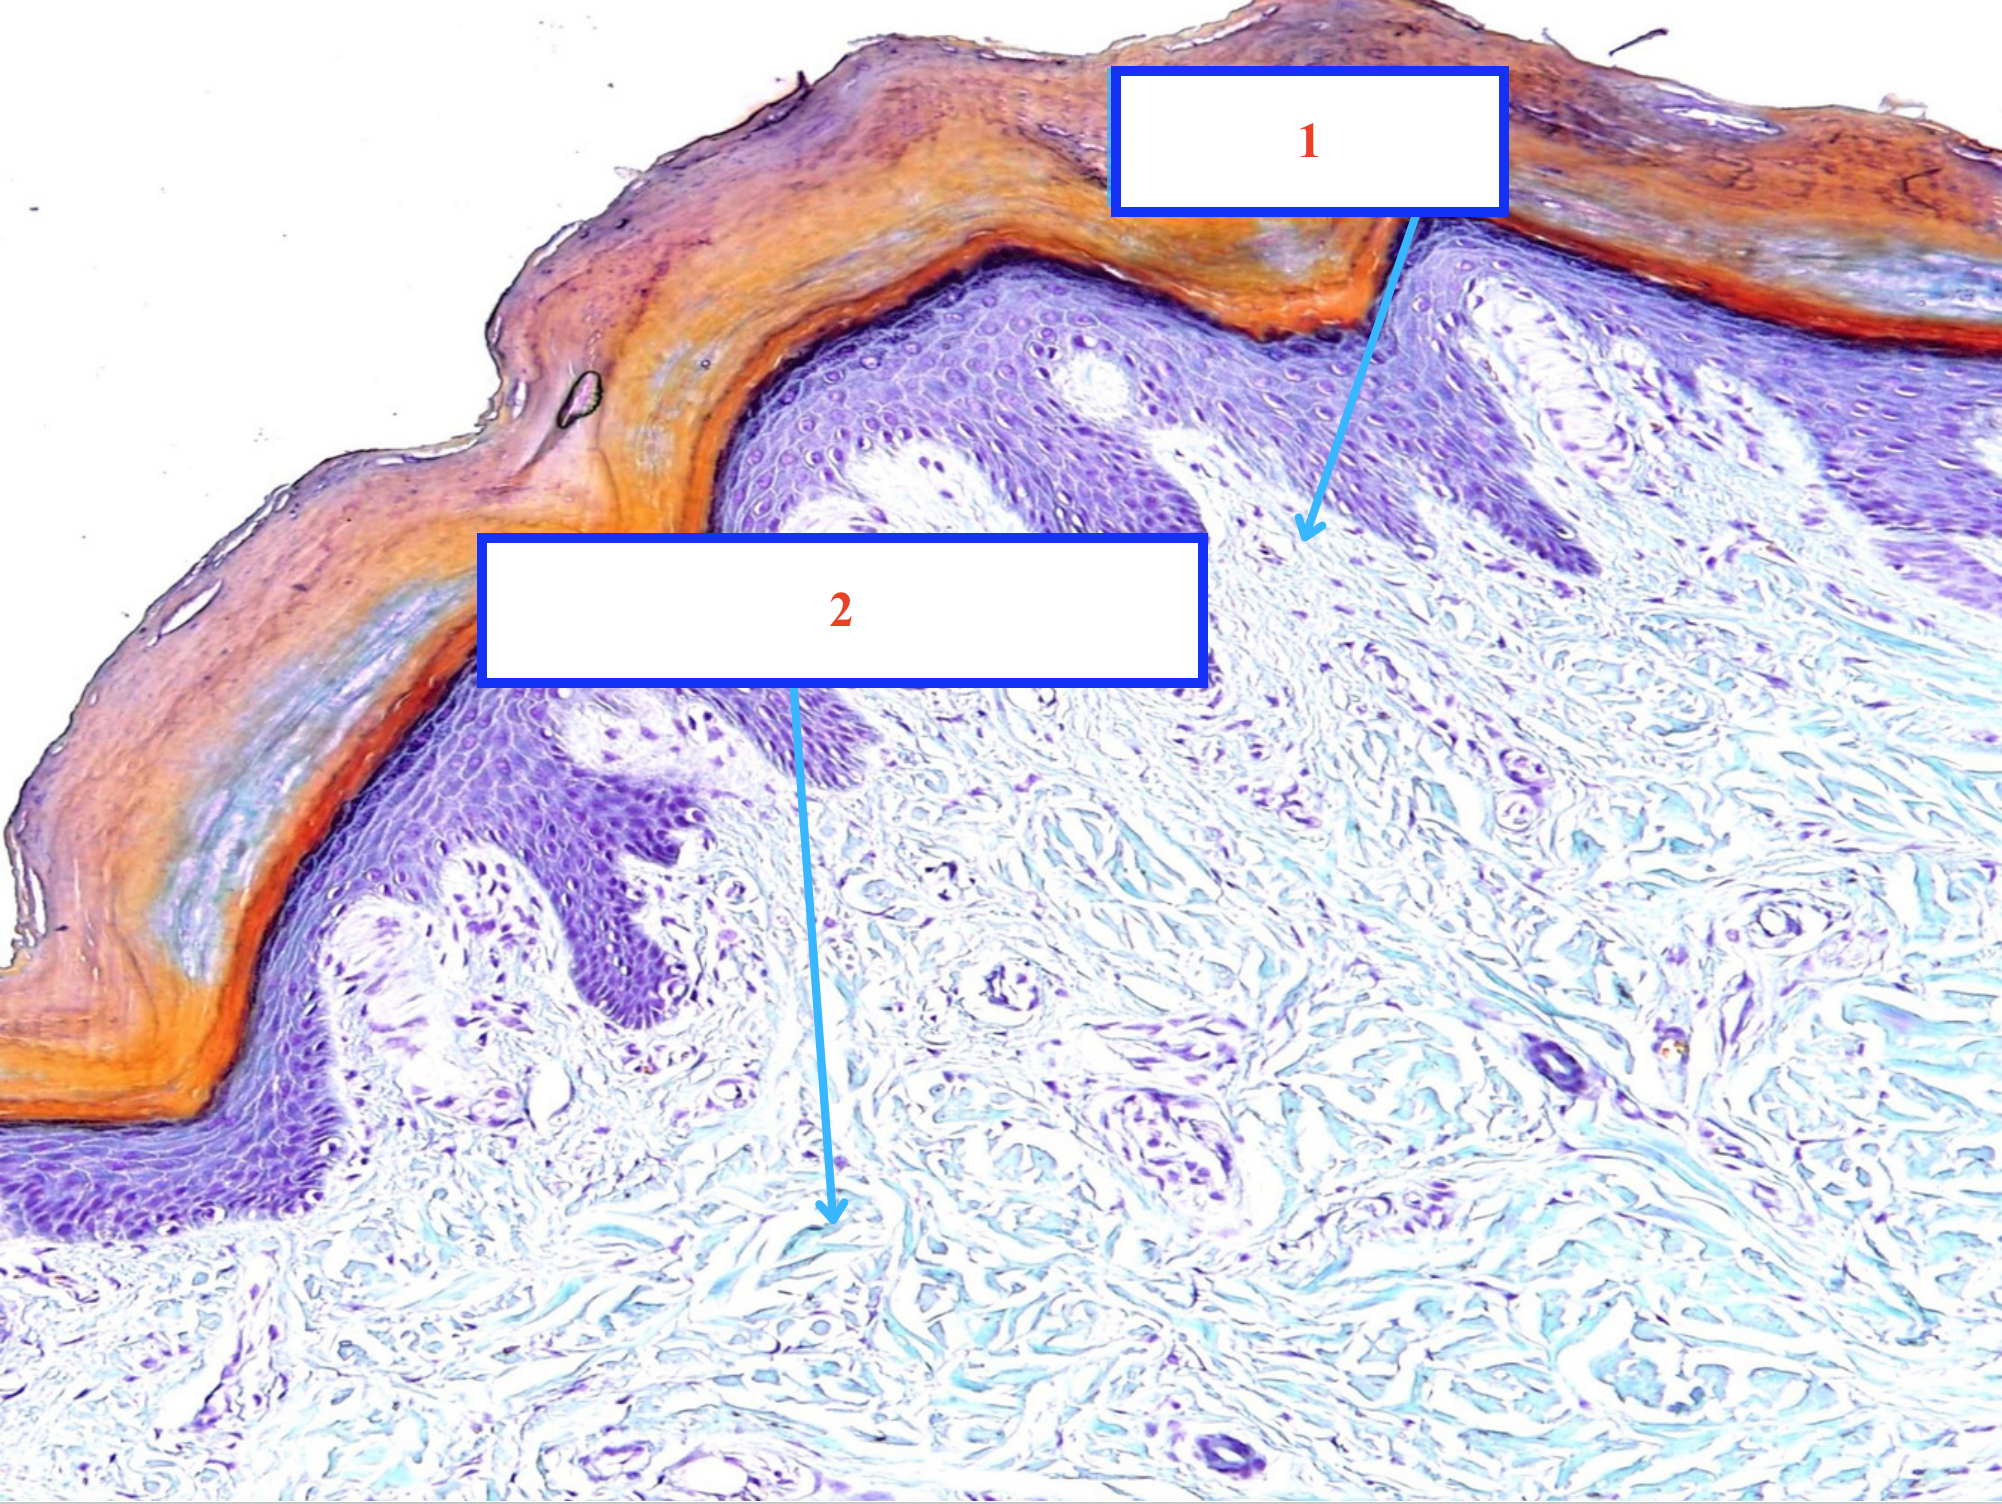

DA:

_Biểu bì:

Phân biệt 5 lớp của biểu mô lát tầng sừng hoá

_Chân bì:

Lớp gì - Tiêu bản gì ?

Lớp sừng của da

Lớp bóng của da

Lớp hạt của da

Lớp gai của da

Lớp sinh sản của da